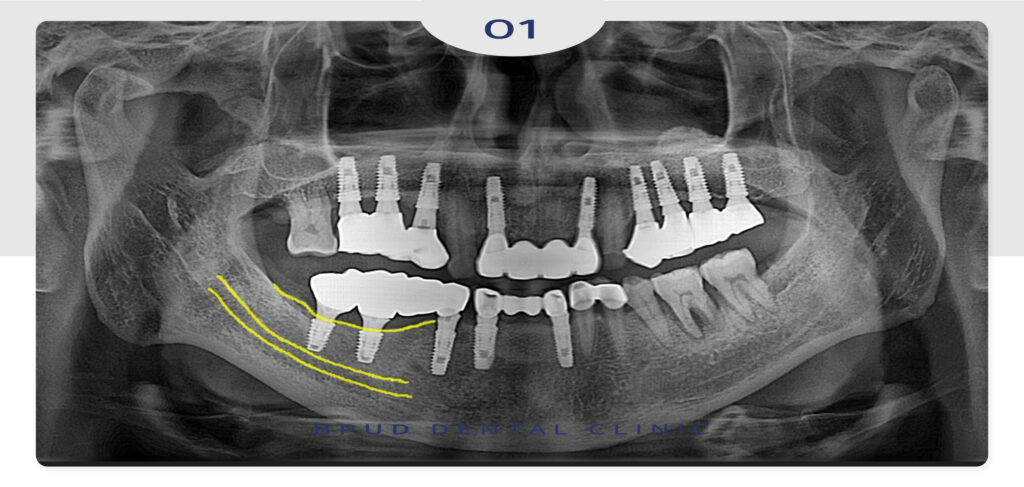

23.10.13

이어서 작은 어금니까지 발치하여

임플란트를 진행하였습니다.

25.02.17

이후에는 정기검진 차 내원하셨을 때에도

잇몸뼈가 잘 유지되고 있는 모습을 확인하였습니다.

환자분께서도 어려운 임플란트를 잘 해결해주셔서

감사하다며 인사를 전해주셨답니다.